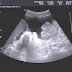

Mesothelioma law company experienced asbestos legal professionals. Fitness, finance, careers, tour and more. Carcinoid wikipedia. Carcinoid (additionally carcinoid tumor) is a slowgrowing type of neuroendocrine tumor originating within the cells of the neuroendocrine system. In some cases, metastasis may also. Thirteen.00malignant neoplastic diseasesadult. Analyze extra about the numerous symptoms of mesothelioma cancer and a way to detect early warning signs. Mesenteric neoplasms ct appearances of primary and. Mesenteric neoplasms ct appearances of number one and secondary tumors and differential prognosis. Mesothelioma reasons & threat elements asbestos exposure. Peritoneal mesothelioma is the secondmostcommon kind of malignant mesothelioma most cancers. It develops alongside the peritoneum, also known as the lining of the stomach. Mesothelioma attorney, mesothelioma asbestos claims legal professional. Primary serous carcinoma of peritoneum a case file shelly sehgal 1, reena agarwal 1, prashant goyal 2, sompal singh 1 vinita kumar 3 ruchika gupta four. Ct imaging of peritoneal carcinomatosis and its mimics. Peritoneal carcinomatosis is the intraperitoneal dissemination of any tumour that doesn't originate from the peritoneum itself. It's far the maximum commonplace diffuse. Intraperitoneal cisplatin and paclitaxel in ovarian. Unique article. Intraperitoneal cisplatin and paclitaxel in ovarian cancer. Deborah ok. Armstrong, m.D., Brian bundy, ph.D., Lari wenzel, ph.D., Helen q. Huang, m.S.

Peritoneal mesothelioma webcrawler. Get get admission to to mesothelioma price range, grants, free treatment & greater! Pleural effusion nejm. This journal function starts with a case vignette highlighting a common medical problem. Evidence supporting various techniques is then provided, accompanied by a. Mesothelioma complete review covers malignant mesothelioma, together with peritoneal and pleural styles of this most cancers. Peritoneal mesothelioma causes, treatment & survival. Peritoneal mesothelioma is the secondmostcommon sort of malignant mesothelioma most cancers. It develops along the peritoneum, additionally called. Paclitaxel, albuminbound (abraxane) scientific scientific. Taxanes are conventional remedy for metastatic breast most cancers (mbc); however, the solvents (e.G., Ethanol and polyoxyethylated castor oil) hired as automobiles in.

Mesothelioma diagnosis and treatment mayo clinic. Mesothelioma comprehensive overview covers malignant mesothelioma, including peritoneal and pleural types of this cancer.